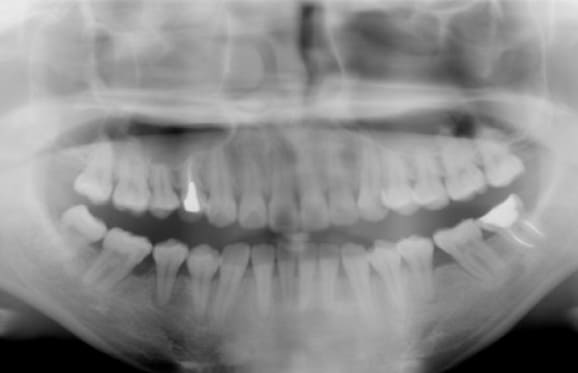

● C4を超え歯根までの虫歯を抜歯、親知らずを利用して歯並び全体を整えた症例

藤沢デンタルオフィスの虫歯や破折で抜歯後の部分矯正